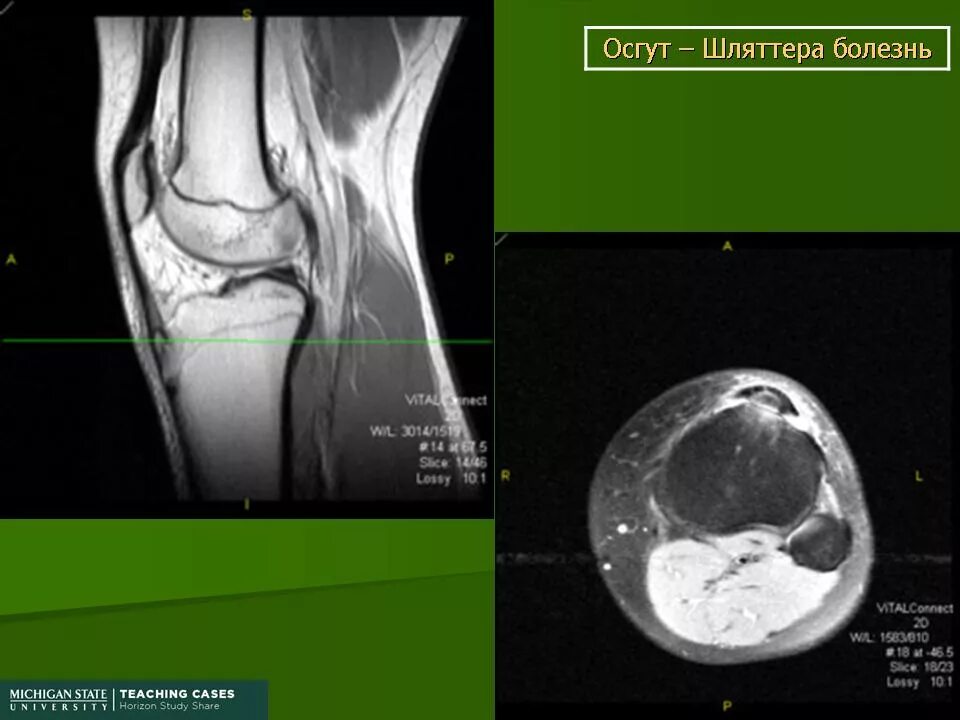

Болезнь осгут шляттера